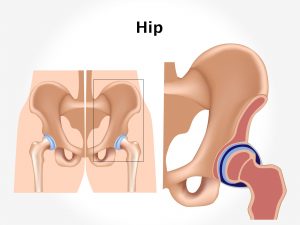

Trauma is one of the major contributing factors for dislocation of the hip. Road accidents or vehicle collision contribute to the injury. Fall from height is another contributing factor. It is also commonly seen in sports where the player strikes the ground while the hip is flexed and adducted. People engaged in sports like football and gymnastics are more prone to such injuries. Hip dislocation is particularly common in snowboarders. A poorly maintained play field can predispose to such injuries. Weak bones and poor strength of muscles makes an individual prone to easy dislocations.

Dislocation of the hip joint is classified into two types. Simple one where there is dislocation of hip, but no fracture is seen, and complex one which is characterized by dislocation along with fracture of acetabulum and femur. Pain in the hip region is the predominant feature seen. Along with this, complete restriction of movement occurs. It can be noticed that the patient is unable to walk. Difficulty in movement or complete immobility often marked with tenderness and swelling is seen. Pain in hip can radiate to the lower leg and back. The patient may also complain of numbness and tingling in the legs in cases of neurovascular damage. Hip dislocations may lead to complications like a nerve injury, arthritis, osteonecrosis, etc.

Diagnosis is done on the basis of the symptoms narrated by the patient and the physical examination carried out by the orthopedic doctor. X- ray of the hip joint is the diagnostic investigation. MRI or CT scan can be done to know the extent of injury and involvement of the surrounding structures.

Rest, application of ice packs, compression, and elevation are the immediate important measures to be implemented. Pain relieving medicines are advised to allay the pain. Surgical intervention is a must for this dislocation. Open or closed reduction method can be adopted. A foot plaster for immobilization is applied. Gradual rehabilitation by physiotherapy is further advised which will help to improve the range and mobility of the joint and strengthen the muscles. Certain yoga exercises can also be helpful in relieving the pain and strengthening the muscles after recovery of the dislocation. Use of walking aids like walkers, crutches help in allaying the pain.